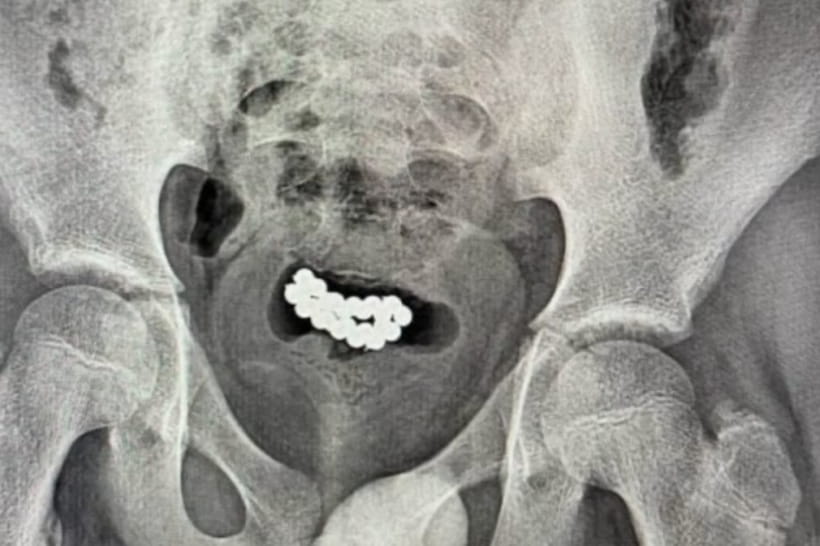

Кілька десятків магнітних кульок розташувалися у сечових міхурах

Кілька десятків магнітних кульок розташувалися у сечових міхурах. Як пояснили хлопці, вони засунули їх всередину себе для посилення відчуттів під час мастурбації.

"За останні три місяці у закладі успішно прооперували два ідентичні випадки евакуації магнітних кульок з сечового міхура хлопчиків віком 10-15 років", – зазначили у центрі.

Хірурги виконали цистотомію міні-лапаротомним доступом та вийняли з організму підлітків 24 та 62 магнітні кульки.